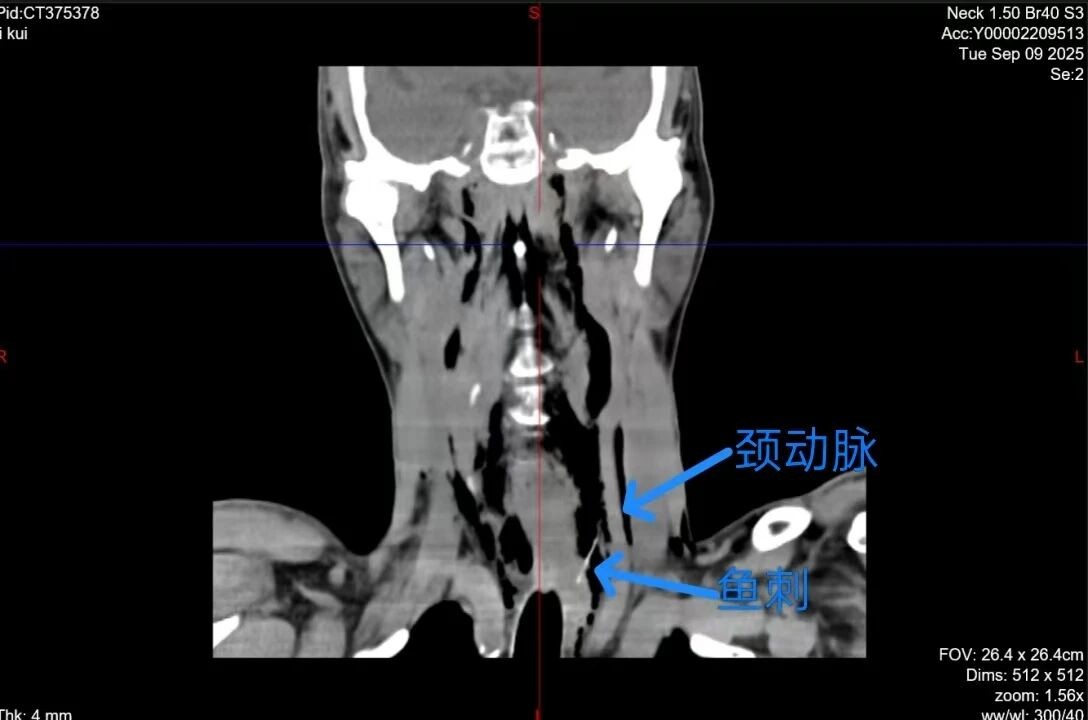

李大哥来院就诊后,经CT检查发现,鱼刺已到深处,一头在食管,一头在颈动脉鞘膜。

主诊医生耳鼻咽喉头颈外科副主任医师陈代波获知情况后,当即决定对李大哥实施手术。术中,医生首先经口食道镜检查,发现李大哥食管侧壁穿孔,但食道内未见鱼刺,又通过食管镜异物钳在食管破口处探查,仍未触及异物。遂考虑食管异物已经刺破食管到颈侧,立即进行颈侧切开,果然,鱼刺被发现。

彼时,鱼刺尖端已刺到颈动脉鞘,头段在食管壁内。凭借丰富的临床经验,医生完整取出长3cm像针一样的鱼刺。缝合食管穿孔后,颈部皮肤采用美容缝合,术后和自身皮纹一样。